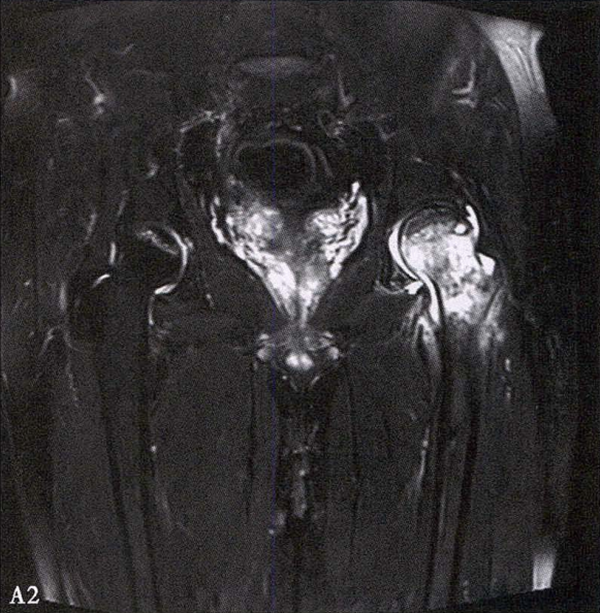

(2)MRI检查 MRI检查是早期诊断股骨头坏死最具特异性、灵敏度的检查方法。当怀疑有股骨头坏死,而X线片无明显异常时,应行MRI检查。诊断时可根据髋关节X线、MRI显示的坏死面积和塌陷程度进行ARCO分期。

冠状面及横断面MRI图像

MRI示双侧股骨头坏死,冠状面显示右侧股骨头坏死(图A、C),横断面显示双侧股骨头坏死(图B、D);T1加权像(图A、B)显示硬化带为低信号,T2加权像(图C、D)显示右侧骨坏死硬化带外围高信号的骨髓水肿,左侧无骨髓水肿。

A.男性,71岁,双侧股骨头坏死,右侧Ⅰ期、左侧Ⅲ期。X线片示双侧股骨头形态可,右股骨头未见明显密度改变,左股骨头关节面下见局限性骨密度减低及增高区(A1)。MRI(T2加权像)示右股骨头内双线征,左侧不规则形混杂信号,坏死区远端骨髓水肿(A2、A3)。